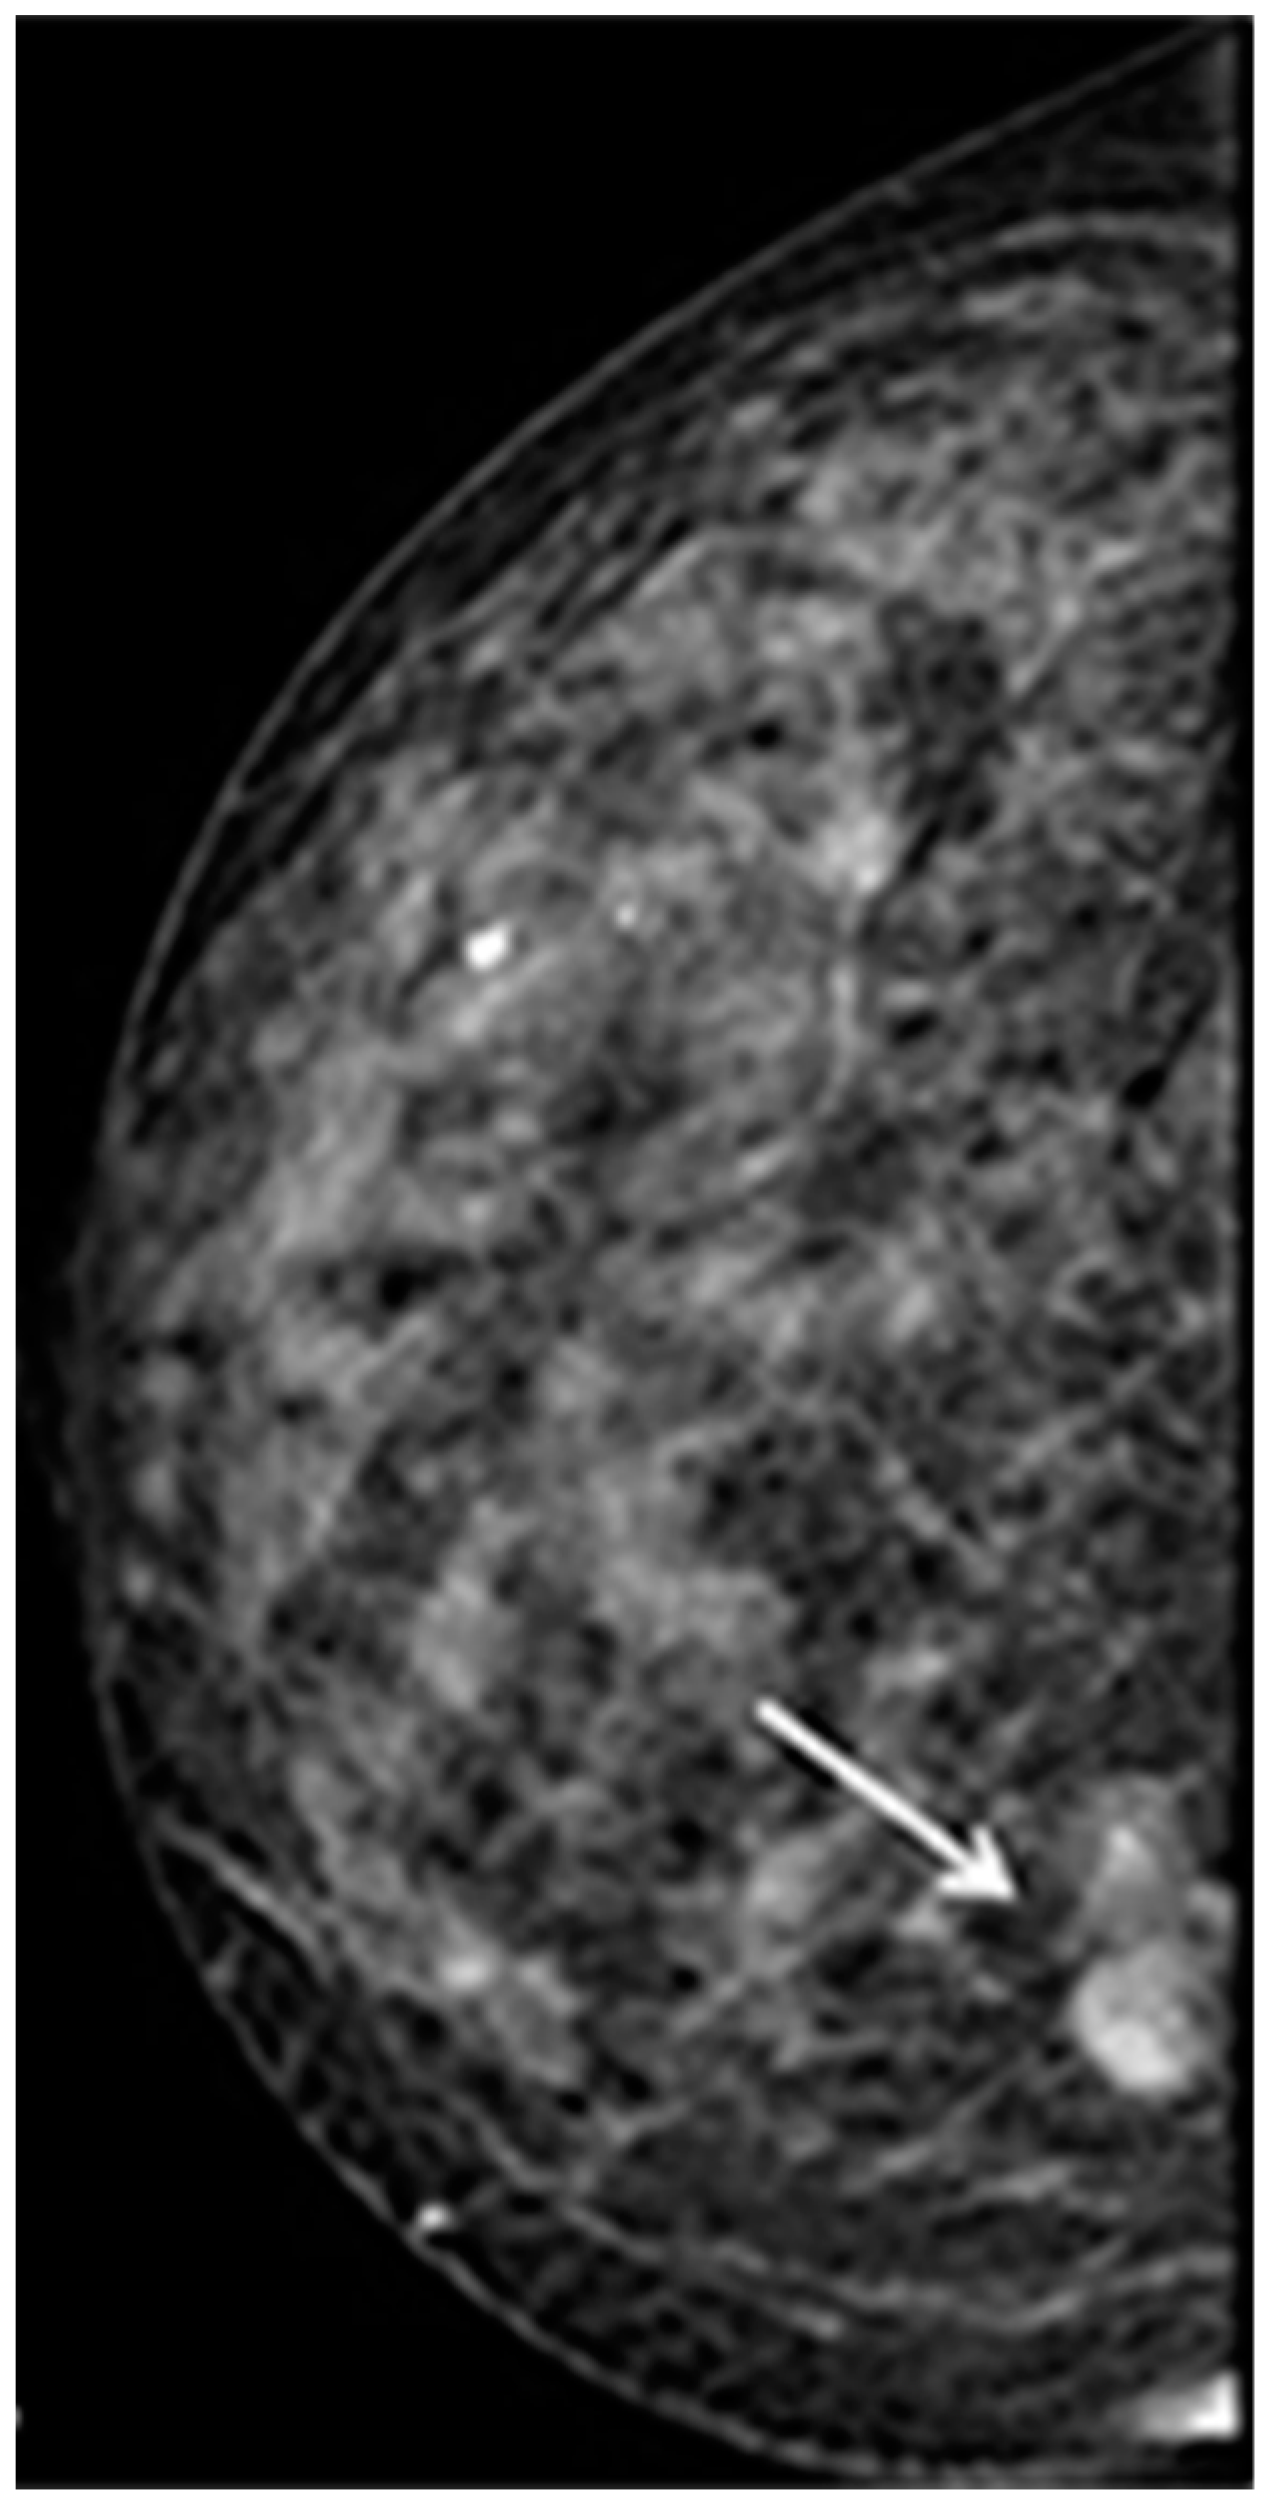

- Lyou, C.Y.; Yang, S.K.; Choe, D.H.; Lee, B.H.; Kim, K.H. Mammographic and sonographic findings of primary breast lymphoma. Clin. Imaging 2007, 31, 234–238. [Google Scholar] [CrossRef] [PubMed]

- Nicholas, S.; Richard, G.B. Sonoelastography of Breast Lymphoma. Ultrasound Q. 2016, 32, 208–211. [Google Scholar] [CrossRef]

- Hoang, J.T.; Yang, R.; Shah, Z.A.; Spigel, J.J.; Pippen, J.E. Clinico-radiologic features and management of hematological tumors in the breast: A case series. Breast Cancer 2019, 26, 244–248. [Google Scholar] [CrossRef] [PubMed]